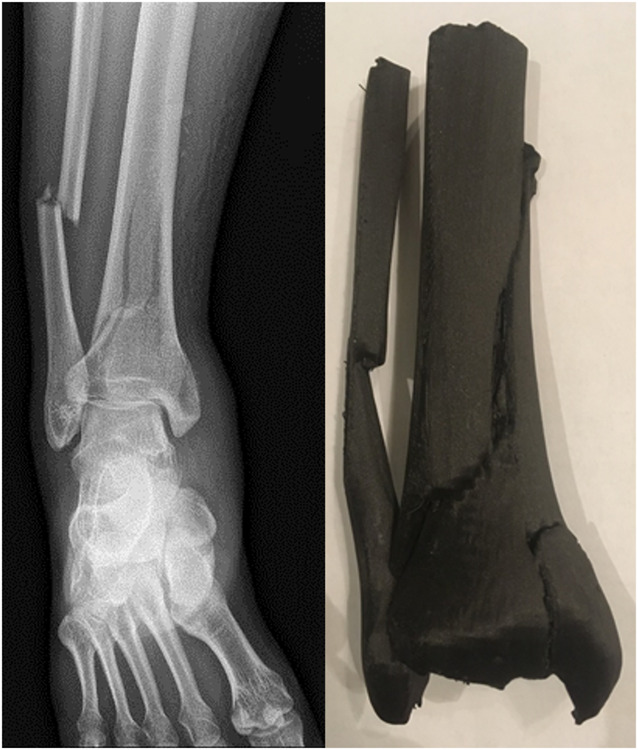

2023年骨科创伤协会的基础科学焦点论坛举办了一场关于骨科增材制造(AM)的研讨会。三位专家介绍了增材制造的各个方面:Malcolm DeBaun博士讨论了用于节段性骨质流失的定制3D打印植入物,Samir Mehta博士探讨了3D打印在教育和手术计划中的应用,Guha Manogharan博士阐述了增材制造和混合制造中的挑战和机遇。研讨会强调了增材制造在骨科创伤的临床、教育和工业应用中的重大影响。

The 2023 Orthopaedic Trauma Association's Basic Science Focus Forum featured a symposium on additive manufacturing (AM) in orthopaedics. Three experts presented on various aspects of AM: Dr. Malcolm DeBaun discussed custom 3D-printed implants for segmental bone loss, Dr. Samir Mehta explored 3D printing in education and surgical planning, and Dr. Guha Manogharan addressed challenges and opportunities in AM and hybrid manufacturing. The symposium highlighted AM's significant impact across clinical, educational, and industrial applications in orthopaedic trauma.